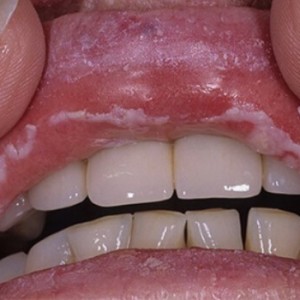

Слизистые оболочки рта покрыты микрофлорой. Молочница в этой области возникает, если грибки рода Candida необычайно активно размножаются. Вследствие чего они проникают в базальный слой эпителия. Со временем начинает появляться белый налёт в ротовой полости, который по своему внешнему виду напоминает молочную пенку. Если её устранить, то слизистая немного отекает и становится ярко-красного цвета.

Кандидоз ротовой полости, это серьёзная проблема, которую нужно решать, не откладывая на завтра, так как она может привести к неприятным, серьёзным последствиям. Первичная форма заболевания проявляется поверхностно. И подвергается быстрому лечению без каких-либо осложнений. Если долгое время не обращать на неё особого внимания, или избавиться от действия неблагоприятного фактора, то болезнь наберёт обороты и перерастёт в хроническую форму (см. фото). Это изрядно скажется на вашей повседневной жизни.

Чтобы определиться с правильным лечением специалист должен для начала изучить симптомы. Первое, что свидетельствует о наличии кандидоза во рту — это белый, густой налёт. Он может быть на слизистых оболочках внутренней стороны щёк, языке, деснах и даже на поверхности глотки. Первым за что берётся врач это определение времени, в течение которого появилась молочница. Легкая отечность и покраснение слизистой оболочки говорит о начальной стадии болезни.

Если при осмотре было выявлено, что оболочка покрыта язвами или на отёчности видны следы крови, то это уже запущенная форма и болезнь существует долгое время. Кроме этого, может быть сухость в ротовой полости, неприятный запах, общая слабость и болевые ощущения при употреблении сладкой, солёной или острой пищи. Не нужно прилагать усилия и самостоятельно снимать бляшки. Лучше обратитесь за помощью к врачу.